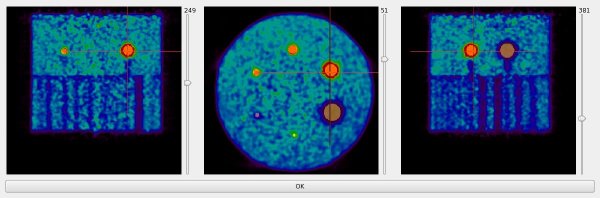

According to possible gap between CT and all PETs, the spheres' mask is computed and displayed like the following :